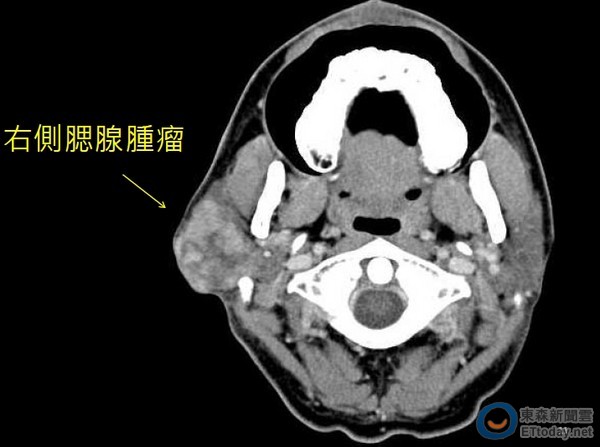

▲電腦斷層掃描發現右側腮腺腫瘤。(圖/記者林悅翻攝)

成大醫院耳鼻喉部張展旗醫師表示,經詳細問診及理學檢查後,初步診斷患者是腮腺腫瘤,再安排電腦斷層掃描,和頭頸部超音波導引下細針抽吸,細胞學檢查懷疑是惡性腫瘤,因此趕緊安排手術完整切除,病理報告顯示是惡性混合瘤。